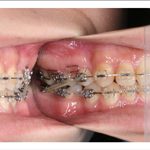

2) 矯正中の状態

叢生(そうせい…歯がデコボコしたり、重なりあって生えていたりする状態)

開咬(かいこう…奥歯はしっかり噛んでいるが、上下の前歯が噛まずに隙間がある状態)